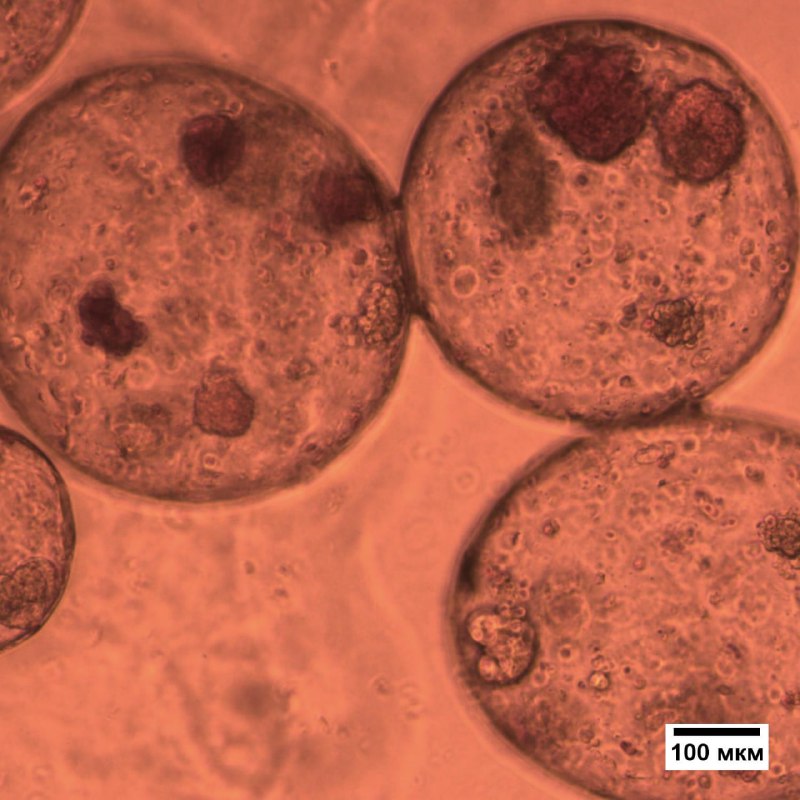

Дефицит инсулина у людей с сахарным диабетом первого типа будут компенсировать гидрогелевые капсулы с инсулин-продуцирующими β-клетками, полученными из стволовых клеток. Препарат не имеет аналогов в России.

Помочь диабетикам могут инсулин-продуцирующие клетки, полученные из плюрипотентных стволовых клеток (ИПСК), их можно неограниченно наращивать в культуре, однако в организме, часто такие клетки погибают под действием иммунной системы. Но российские ученые придумали, как этого избежать.

Ожидается, что капсулы защитят инсулин-продуцирующие клетки от разрушения при трансплантации и иммунного ответа за счет механической поддержки и полупроницаемой мембраны. В капсулы будут встроены биомолекулы и факторы роста, они улучшат выживание и функционирование β-клеток, а клетки взаимно защитят материал капсулы от иммунной реакции, выделяя противовоспалительные цитокины,

Структуру и свойства микрокапсул ученые подберут путем 3D-моделирования, а оптимальные варианты дополняющих друг друга β-клеток и микрокапсул определятся после тестирования in vitro и in vivo. Тестировать лекарство будут в НИИ экспериментальной онкологии и биомедицинских технологий ПИМУ.